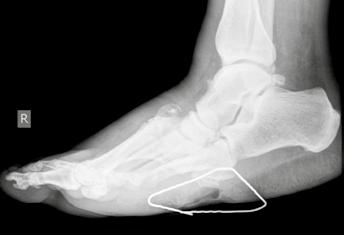

- Typ V: Diese seltene Verlaufsform der DNOAP betrifft den Calcaneus und das dazugehörige talocalcaneare Gelenk. Es führt zum Zusammenbrechen dieses Gelenkabschnittes mit der zwangsläufigen Verplumpung des gesamten Rückfußes oder zu Schnabelfrakturen des Calcaneus, bedingt durch den Zug der Achillessehne.